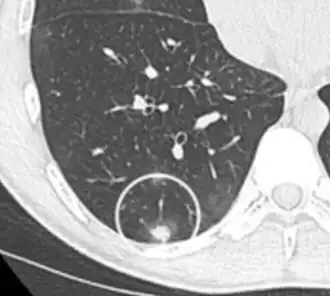

Low attenuating nodule (in this case a fat containing hamartoma).[9] -

Cavitation with relatively thick wall, in this case aspergilloma).[9]

- In case of calcifications, a popcorn-like appearance indicates a hamartoma, which is benign.[3]